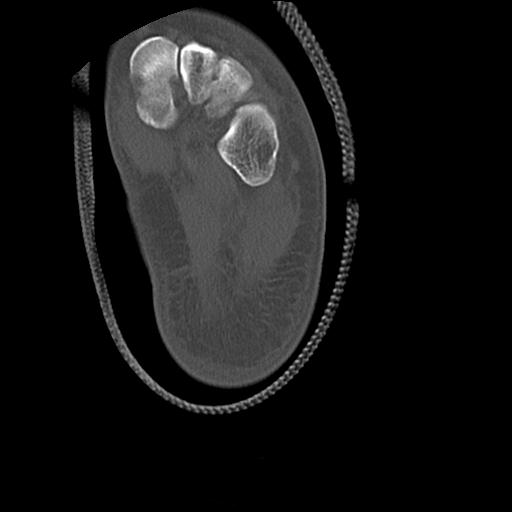

102755 1/4 2R 1/15 2R 右足関節 68歳女性 右三果脱臼骨折